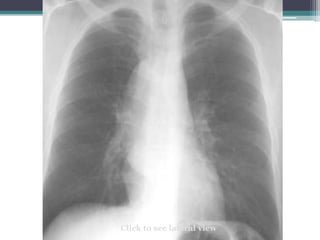

Which compartment do you think this mass is in?

Click for answer

Mass

โ€œdisappearsโ€

at clavicle

โ€ข Answer: Mass lies in anterior mediastinum. We

know this because it disappears at the level of the

clavicle where it extends into the neck.

โ€ข This particular example is Non-Hodgkins lymphoma